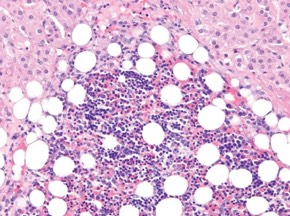

1095. Опухоль надпочечника на разрезе выглядела как округлый узел желтого цвета с участками бурого цвета, без капсулы, 5 см в наибольшем измерении. по гистологическому строению опухоли, приведенному на микрофотографии, диагнозом является